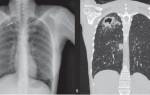

Пневмония является частым осложнением после микоплазмоза.

В случае, если в организме питомца действительно развивается инфекция, лабораторные исследования выявляют анемию – пониженное содержание красных кровяных тел.